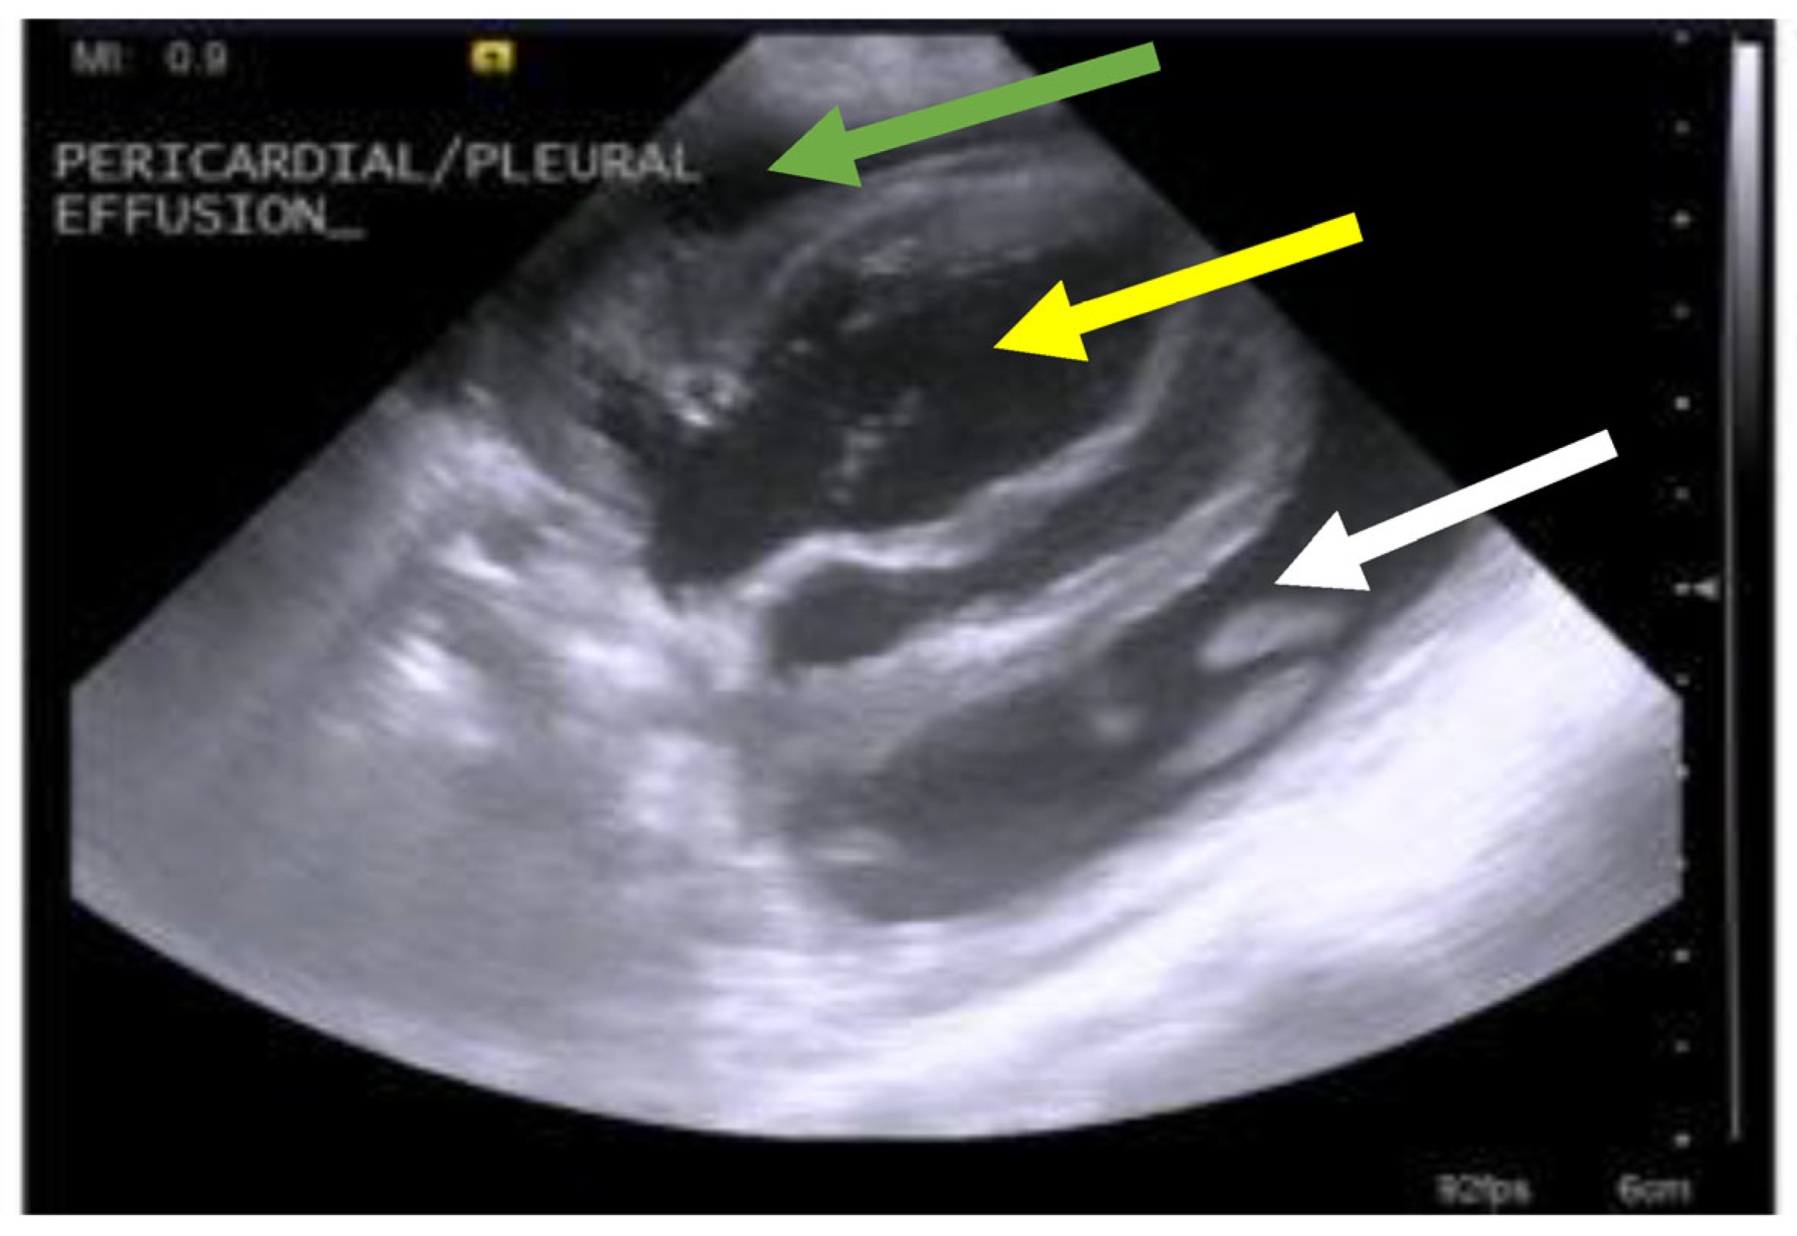

7.4. Diagnostic Imaging in FIP

7.4.1. Routine Imaging: Ultrasonographic and Radiographic Findings

| Summary of Section 7: Diagnosis of FIP; Section 7.4: Diagnostic imaging in FIP: No specific ultrasonographic or radiographic findings exist for FIP. Ultrasonography (in particular) and radiography can show the presence of effusions. Pneumonia due to FIP that is occasionally reported can be associated with radiographic changes. Ultrasonography can reveal abdominal lymphadenomegaly or lymphadenopathy and/or abnormalities of the liver, spleen, intestines and/or kidneys (which can include a medullary rim sign), depending on which organs are affected. Imaging can also be of use to the direct sampling of abnormal tissues, e.g., fine-needle aspirate for cytology examination to reveal non-septic pyogranulomatous inflammation, or ultrasound-guided needle core (e.g., tru-cut) biopsies can be collected and submitted for histopathology. When a cat is showing neurological signs, the imaging of the brain by magnetic resonance imaging, if available, with contrast, can be useful to demonstrate neurological abnormalities (such as obstructive hydrocephalus, syringomyelia, foramen magnum herniation and marked contrast enhancement of the meninges, third ventricle, mesencephalic aqueduct, and brainstem). A description of computerised tomography findings in cats with neurological FIP has not been published, but MRI is likely to be more sensitive in the detection of subtle intraparenchymal lesions. Advanced imaging of the central nervous system is indicated before performing cerebrospinal fluid sampling to assess the potential risk of herniation. |